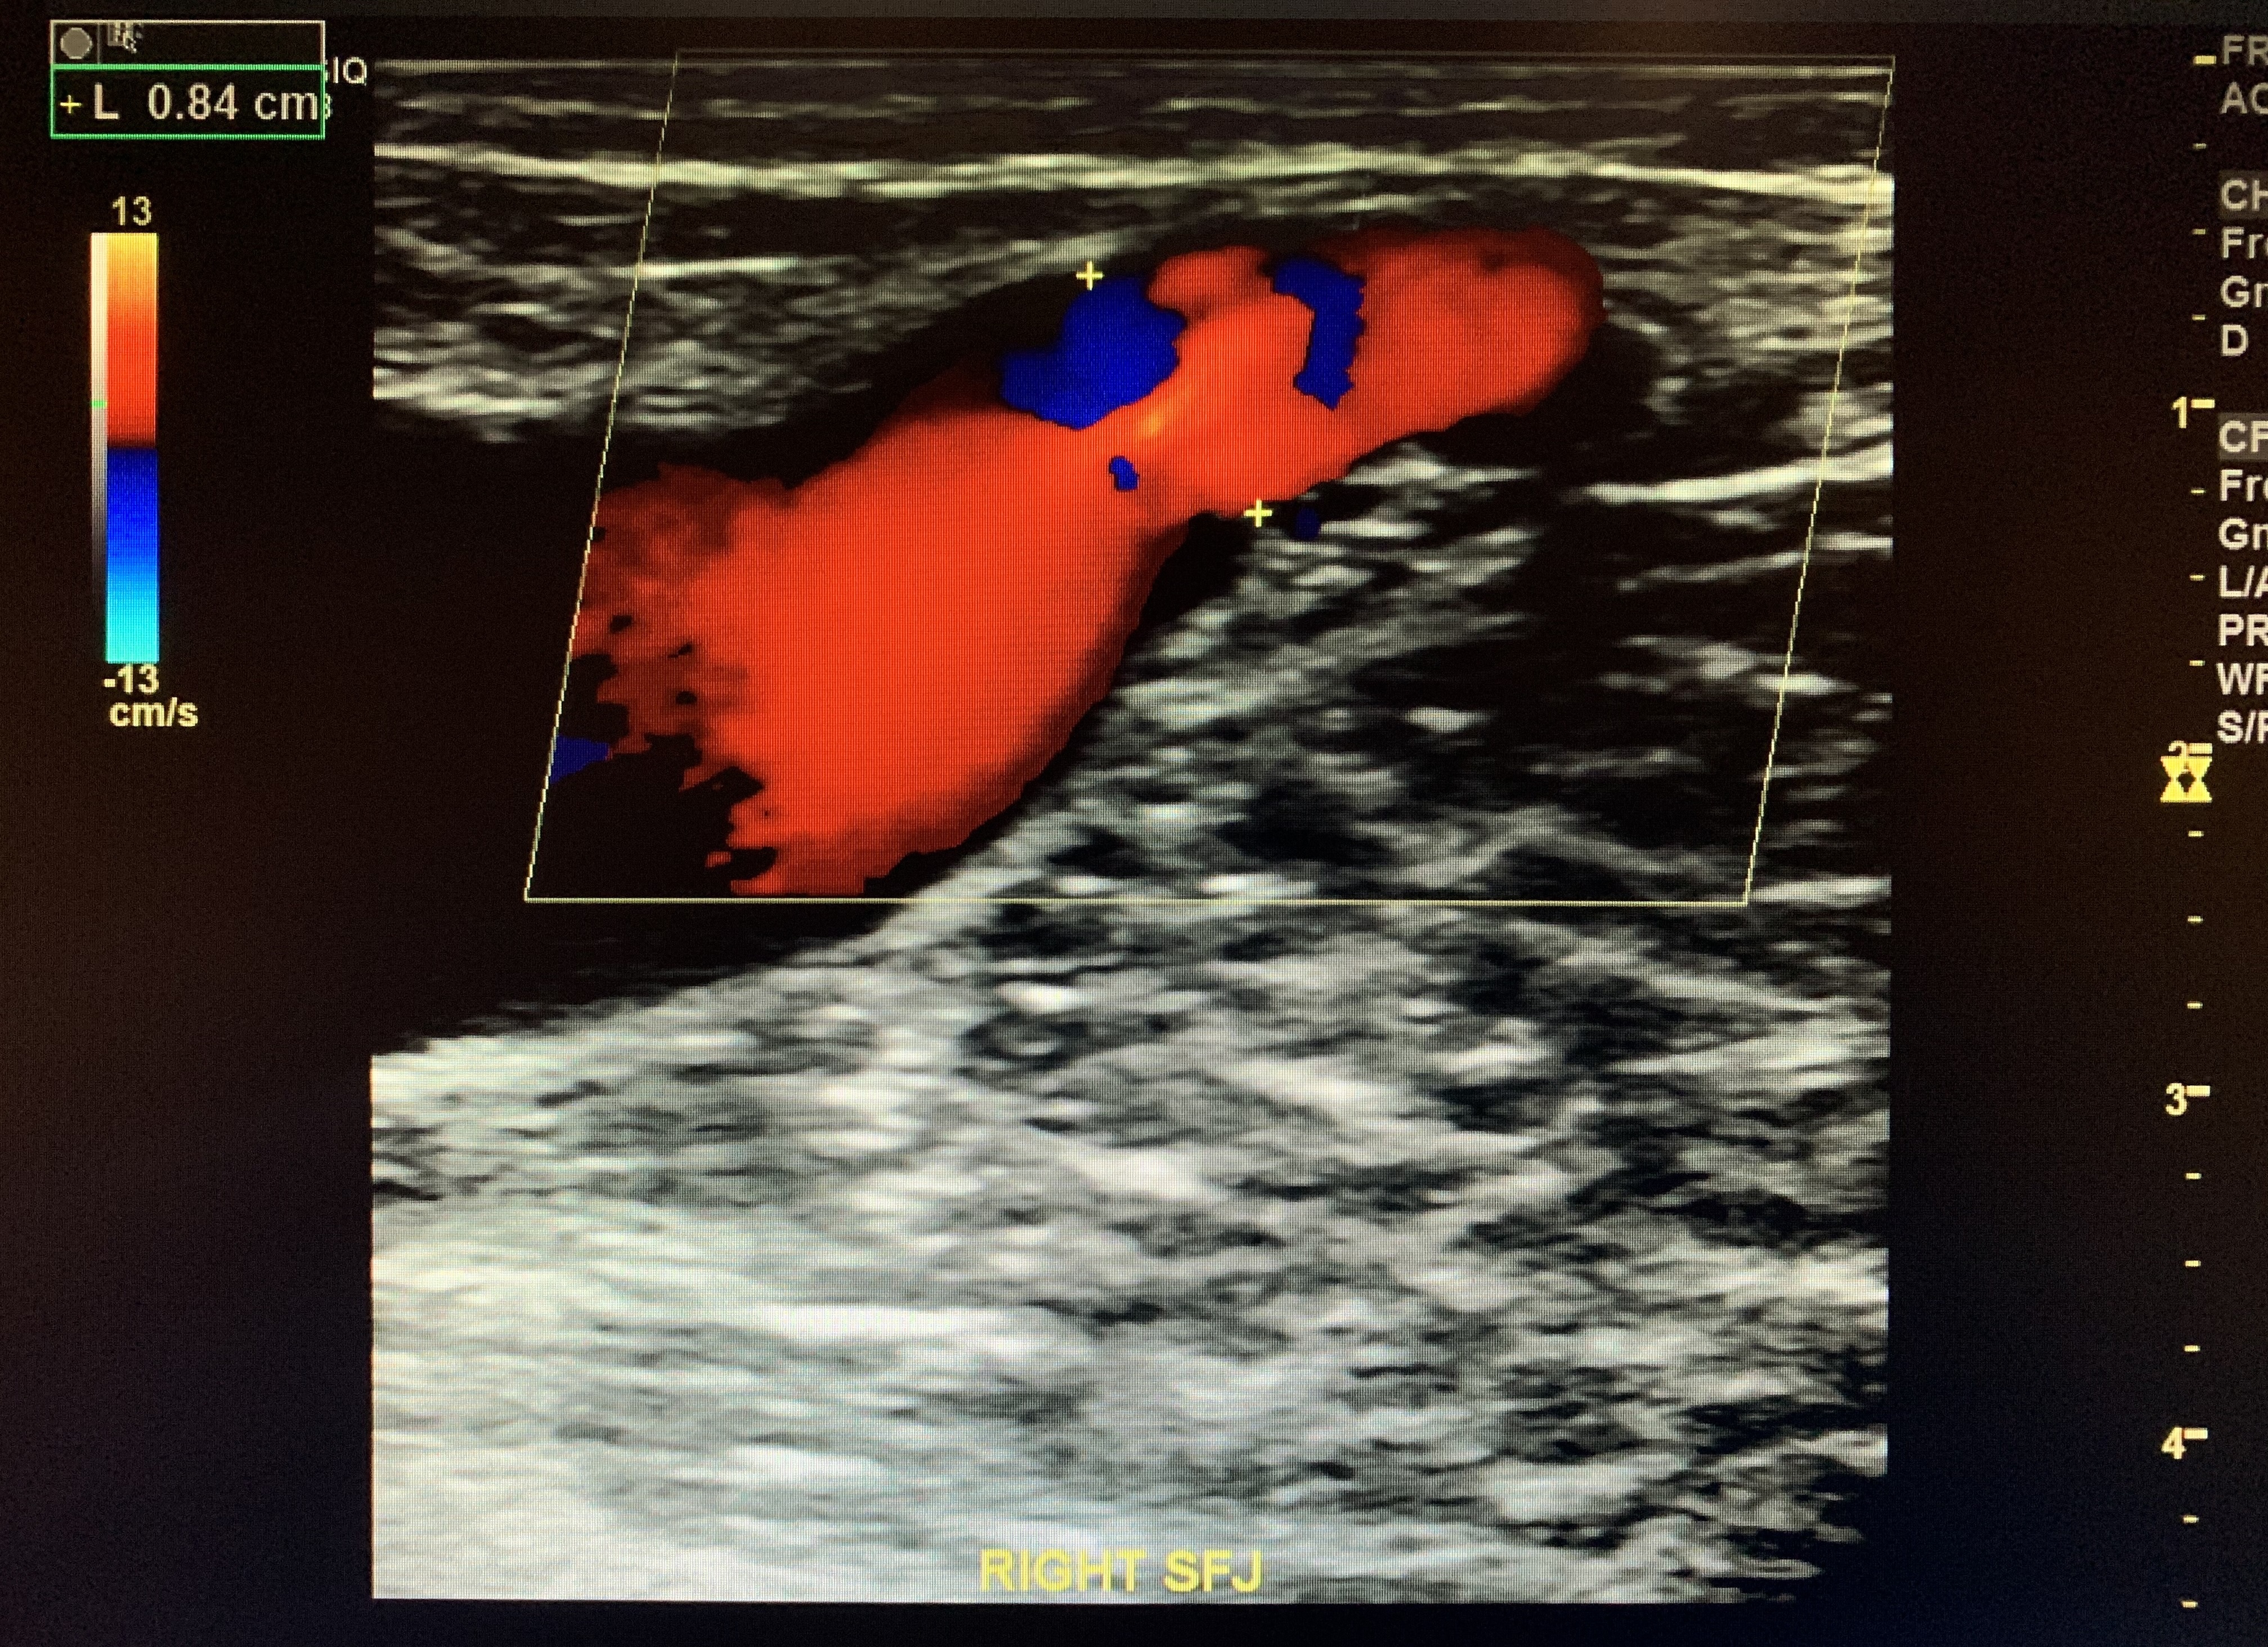

Sapheno-Femoral Junction

Ask the patient to perform the valsalva technique by having them bare down and strain.

This should elicit retrograde flow if the SFJ is incompetent. Positive reflux is >0.5 seconds for all superficial veins.

This patient demonstrates a considerably severe reflux in the SFJ (up to 4 seconds) performed w/ valsalva.

Measure the sapheno-femoral junction. In this case it is 8.4mm.